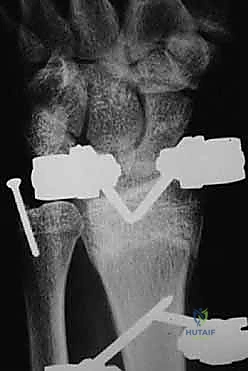

ثانياً: العلاج الجراحي (Surgical Intervention)

متى يقرر الدكتور هطيف ضرورة التدخل الجراحي؟

1. عدم الاستقرار (Instability): إذا كان المفصل الزندي الكعبري البعيد (DRUJ) غير مستقر بعد تثبيت كسر الكعبرة.

2. الانزياح (Displacement): إذا كان الكسر في قاعدة الناتئ الإبري منزاحًا بأكثر من 2 ملم.

3. الكسور المفصلية: أي كسر يخل بتطابق السطح المفصلي لرأس الزند.

4. الكسور المفتتة: في الجزء الكردوسي التي تؤدي إلى قصر عظم الزند.

التخطيط الجراحي لكسور الزند

خطوات التدخل الجراحي الدقيق مع الأستاذ الدكتور محمد هطيف

تُعد جراحات المعصم والزند من الجراحات الدقيقة التي تتطلب مهارة عالية، وهو المجال الذي يتفوق فيه الأستاذ الدكتور محمد هطيف بفضل استخدامه لتقنيات الجراحة المجهرية (Microsurgery) والأدوات الجراحية ذات التقنية العالية.

1. التخطيط ما قبل الجراحة (Pre-operative Planning)

يقوم الدكتور هطيف بدراسة الأشعة المقطعية ثلاثية الأبعاد بدقة، ويختار نوع وحجم الصفائح المعدنية (Plates) والمسامير (Screws) المناسبة لكل مريض بناءً على حجم العظم ونوع الكسر.